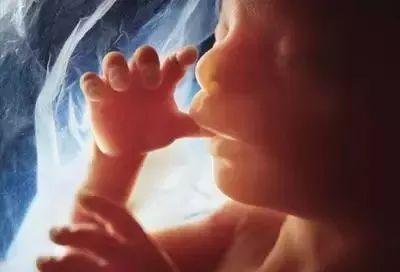

三个月:胎儿的身体为7-9厘米,重约20克,与4-7周相比,胎儿增加了3.4倍以上,躯干和腿部全部发育,头部明显较大,下颚和颊部发达,更重要的是鼻子、嘴唇、根。声带已经长了,脸部更像脸部,眼睛已经被比较了。眼睑生长。它能对外界刺激作出反应。如果你用手戳你的胃,它甚至会移动,但在几周内,你就感觉不到他的活动。胎儿肠生长很快,其中一些进入脐带。他们开始转移到腹腔。胎儿的肾脏分泌尿液进入膀胱。

四个月:胎儿长度约13~17 cm,体重约125克。骨骼系统进一步发育,胎盘完全形成,胎儿肢体活动,母亲感觉胎儿运动,肌肉发达。虽然胎儿的毛发还没有出现,他的头皮结构已经开始发育。虽然他仍然闭上眼睛,他的眼球可以缓慢移动,甚至开始有长长的指甲。